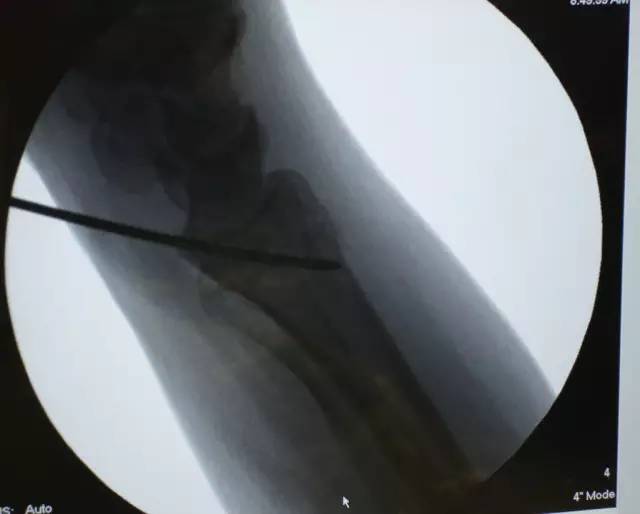

1. 经桡侧腕屈肌和桡动脉之间完成显露后,将一枚光滑的克氏针置入到桡腕关节:

6. 应用 X 线透视确认钢板和远排螺钉的位置: